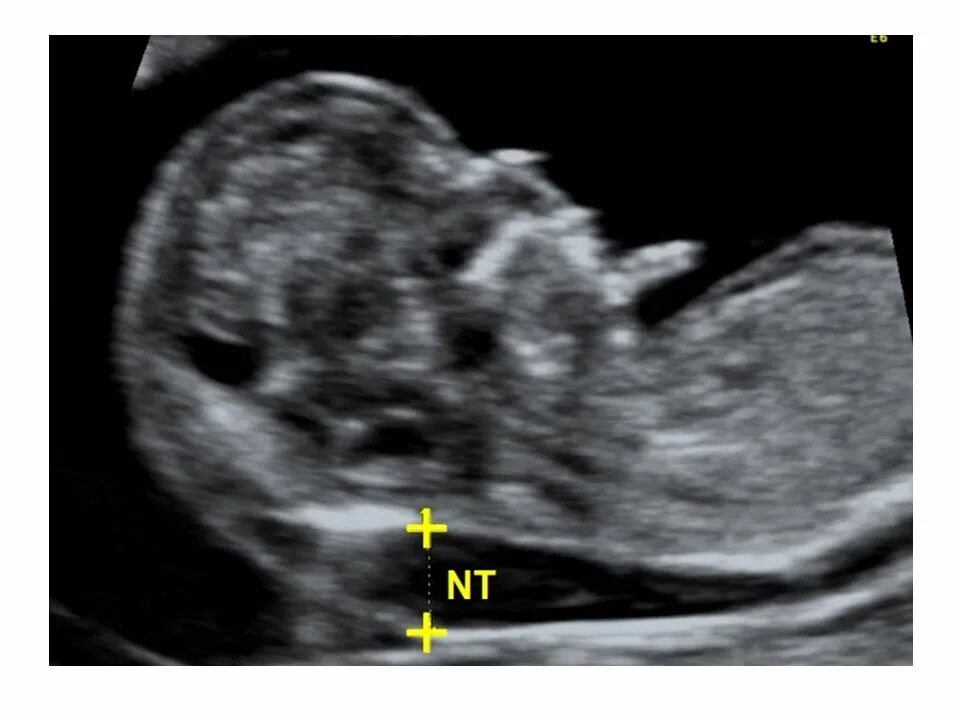

Воротниковое пространство норма